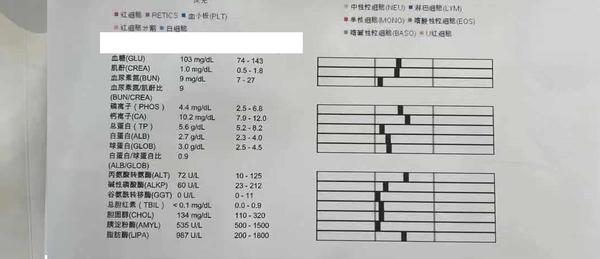

到医院后医院没有仔细看资料,开了7个检查“生化、血常规、4张X光、1组B超、胰腺炎测试、C反、粪便化验”,就是不肯做胃镜检查。宠物主人不好意思反对医生的意见所以7个化验花了2000元。化验结果和我们预料的一样,每一个都没有问题,甚至可以说狗的身体结果是完美的,血常规和生化里没有任何一项指标高或者低(健康狗里都很少),其中2张片子还是照心脏的。

过去半年主人带狗做过多次生化,血常规、粪便检查,有的医院说肠胃菌落失调,有的没有结果。我们经过对化验单的分析,和症状表现按出血型肠胃炎(不是肠胃炎出血)治疗,治疗后最近都没有拉血表现 ,但是14-15天一次的呕吐还是无法找到原因。另外出血型肠胃炎是很少见的疾病,成因目前医学上还未知,根据分析我们认为最大可能是在胃部,担心会出现肿瘤或者未来有溃疡引起的穿孔,所以我们说服宠物主人给狗在当地比较好的医院做一次胃镜确定问题出在那里,在北京大概1000元所以我们认为费用在可以接受范围里。